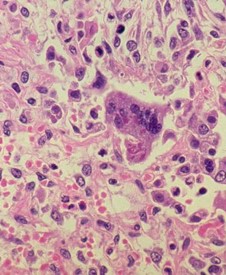

A photomicrograph of a lung tissue specimen reveals the histopathologic changes encountered in a case of measles pneumonia. Numerous leukocytes and multinucleated giant cells with intracytoplasmic inclusions were observed.

Increased plasma levels of Th1-dependent interferon-gamma during the acute phase and subsequent increases in Th2-dependent interleukin 4, interleukin 13 levels, and interleukin 10 cellular immune responses are crucial for recovery. The typical Warthin-Finkeldey large cells in lymph node biopsy are seen against a paracortical hyperplasia background.